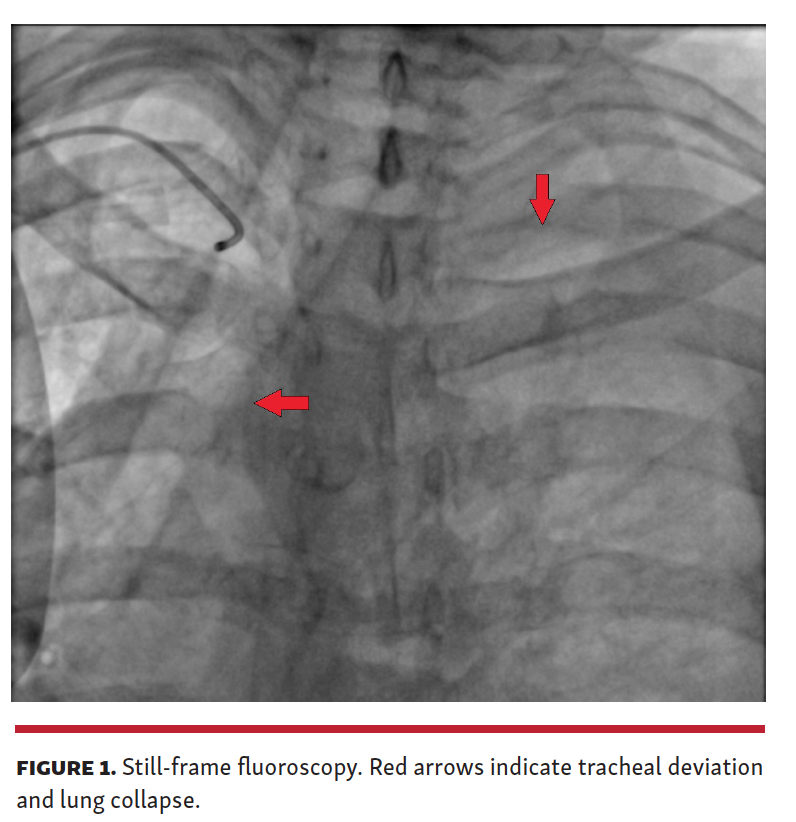

On fluoroscopy of the chest, our radiographer brought to attention gross tracheal deviation and collapse of the left lung (Figure 1 and Video 1). The right coronary artery was rapidly engaged, and a culprit proximal lesion was identified with Thrombolysis in Myocardial Infarction 3 flow beyond. On left ventriculogram, the ventricle was small and hyperdynamic. A chest drain was inserted on the cath lab table by the thoracic surgeon and confirmed the presence of a large left hemopneumothorax. PCI was deferred due to the acute hemorrhage and presence of normal coronary flow, and the patient was transferred to the intensive care unit for further management. Bleeding from within the lower lobe of the left lung was found on computed tomography, which ceased with administration of platelets and fresh frozen plasma. This case highlights the importance of maintaining a broad differential diagnosis and of harnessing the various skills within a multidisciplinary team.